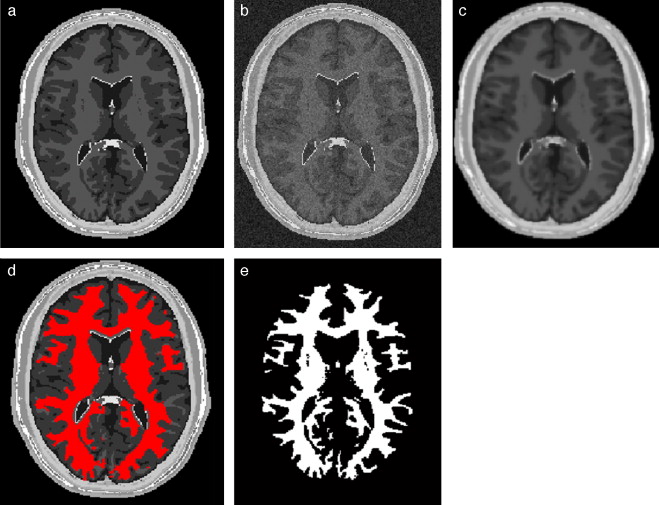

4.2. Caso 2: segmentación Watershed - BrainWeb

Al igual que el caso anterior, el esquema de segmentación Watershed fue validado empleando el phantom de IRM del cerebro. En la figura 25 se presentan los resultados obtenidos al segmentar la zona de la materia blanca en el volumen phantom con dimensiones de 181 × 217 × 181 (X × Y × Z ), con voxels isotrópicos de 1,0 mm3 . En la figura 25 .a se presenta el corte número 98 de la imagen original. En la figura 25 .b se presenta la segmentación obtenida empleando el algoritmo de Watershed . En la figura 25 .c se presenta la zona de la materia blanca proporcionada por BrainWeb.

|

|

|

Figura 25. Materia blanca segmentada en volumen phantom de IRM del cerebro. (a) Corte axial 98 de imagen de phantom original. (b) Materia blanca segmentada con metodología propuesta empleando algoritmo Watershed. (c) Zona de la materia blanca segmentada por BrainWeb . |

Para validar los resultados, se empleó el análisis de texturas, calculando los descriptores estadísticos en los volúmenes obtenidos. En la tabla 2 se presentan los valores estadísticos y los respectivos porcentajes de error para ambos volúmenes. Obsérvese que el porcentaje de error del número global de pixels no supera el 1,2418%, y para los descriptores estadísticos no supera el 1,5201%.

| Nro. pixels | Media | Desviación estándar | Asimetría | Homogeneidad | Entropía | |

|---|---|---|---|---|---|---|

| Watershed | 683.262 | 0,0961 | 0,2947 | 2,7406 | 8,5110 | 0,4565 |

| Phantom BrainWeb | 674.777 | 0,0949 | 0,2931 | 2,7641 | 8,6404 | 0,4527 |

| %error Watershed-phantom | 1,2418 | 1,2418 | 0,5573 | 0,8576 | 1,5201 | 0,8479 |

4.3. Caso 3: filtrado de difusión anisotrópica y segmentación Region Growing - BrainWeb

En este caso, se corrompió el volumen phantom con ruido aditivo gaussiano y se procedió a aplicar las rutinas de filtrado y segmentación. Para suavizar el ruido de la imagen, se aplicó la rutina de filtrado con difusión anisotrópica (sección 2.2.1) y la segmentación de la zona de la materia blanca fue realizada con la rutina Region growing (sección 2.3.2). El flujograma de técnicas empleadas es similar al presentado en la figura 21 .

En la figura 27 se presentan los resultados obtenidos al segmentar la zona de la materia blanca con las rutinas y mencionadas. En la figura 27 .a se presenta la imagen phantom original, mostrando el corte axial número 98 del phantom . En la figura 27 .b se presenta la imagen phantom con ruido aditivo gaussiano. En la figura 27 .c es mostrada la imagen resultante luego de filtrar (b) con el filtro de difusión anisotrópica, además se observan las 5 semillas (seed points) seleccionadas de manera arbitraria sobre el área de la materia blanca. Las semillas empleadas tenían forma esférica de 2 pixels de radio, con el centro en las coordenadas X,Y,Z , las coordenadas de las semillas son: Seed1= (65,59,98), Seed2 =(112,55,98), Seed3 =(117,104,98), Seed4 =(127,137,98), Seed5 =(55,128,98). En la figura 27 .d se presenta el resultado de la segmentación (en rojo). En la figura 27 .e se presenta la zona de la materia blanca proporcionada por BrainWeb.

|

|

|

Figura 27. Materia blanca segmentada en volumen phantom . (a) Corte axial número 98 de imagen de phantom original. (b) Imagen original con ruido gaussiano agregado (c) Imagen con ruido filtrada con filtro de difusión anisotrópica. (d) Materia blanca segmentada con algoritmo Region Growing con 5 semillas esféricas. (e) Zona de la materia blanca segmentada por BrainWeb . |

Se calcularon los valores estadísticos y los respectivos porcentajes de error entre el volumen segmentado y el volumen proporcionado por BrainWeb, los resultados son presentados en la tabla 3 . Obsérvese que el porcentaje de error del número de pixels global no supera el 3,6374%, y para los descriptores estadísticos no supera el 7,1608%.

| Nro. pixels | Media | Desviación estándar | Asimetría | Homogeneidad | Entropía | |

|---|---|---|---|---|---|---|

| Difusión anisotrópica-Region Growing | 650.232 | 0,0899 | 0,2910 | 2,8739 | 9,2591 | 0,4351 |

| Phantom BrainWeb | 674.777 | 0,0949 | 0,2931 | 2,7641 | 8,6404 | 0,4527 |

| %error Region Growing-phantom | 3,6374 | 5,2687 | 0,2100 | 3,9702 | 7,1608 | 3,8745 |